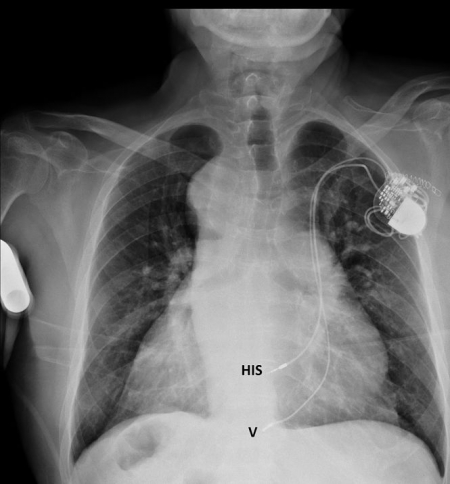

Aplican una técnica de estimulación fisiológica a un centenar de pacientes con fallo cardiaco

Esta técnica conocida como la estimulación hisiana ha emergido en los últimos años y se caracteriza por usar las vías eléctricas presentes en el corazón